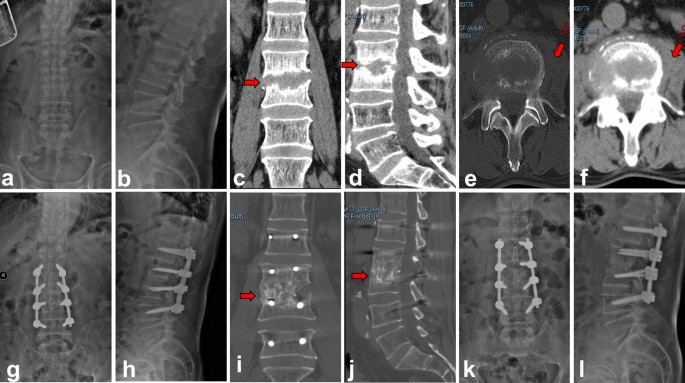

The comparison of the fusion rate, average fusion time, lumbar lordosis and sagittal angle results between group A and group B were summarized in Table 2 and representative radiological images of one patient in each group were shown in Figs. 3 and 4. The mean preoperative lumbar lordosis angles of group A and group B were 45.7° ± 8.9° and 44.1° ± 10.0°. These were corrected to 51.2° ± 7.2° (P < 0.05) and 52.6° ± 7.7° (P < 0.05) at the last follow-up, respectively. The mean preoperative sagittal Cobb angle of group A was 5.9° ± 3.3°. This was corrected to 14.1° ± 4.9° (P < 0.05) after the immediate operation. There was a mean loss of 4.6° in the follow-up period and the mean sagittal Cobb angle was 9.5° ± 3.2° at the last follow-up. In Group B, the mean preoperative sagittal Cobb angle was 6.1° ± 4.9°. This was improved to 15.5° ± 5.0° after immediate surgery and 11.5° ± 5.0° at the final follow-up (with a mean loss angle of 3.75°), indicating a significant correction. Compared with the preoperative values, the mean sagittal Cobb angles of group A and group B were significantly improved at the last follow-up.

Autologous iliac bone group (group A). A 68-year-old male with L3–4 lumbar pyogenic spondylitis (a–f). Preoperative X-ray and CT showed that L3–4 vertebral body destruction with sequestrum formation, intervertebral space stenosis and psoas abscess (red arrow). (g,h) Postoperative X-ray showed iliac bone graft and internal fixations were in good location. (i–l) CT and X-ray taken at 6 months after operation showed solid bone fusion between L3 and L4.